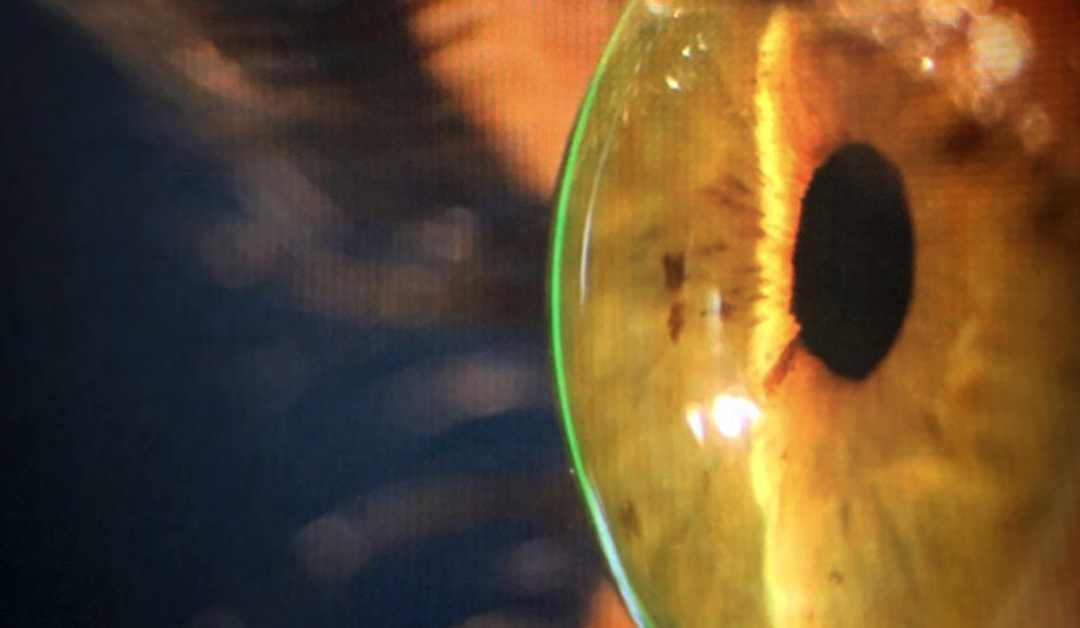

CONTROL DE ABERRACIONES CON LENTES DE APOYO ESCLERAL

Luis Izquierdo MD,Oftalmólogo Edward Carmona, O.D.NCLE-AC – FSLS Los errores refractivos como la hipermetropía, miopía y astigmatismo son condiciones conocidos como aberraciones de bajo orden. Estos generalmente se corrigen con gafas o lentes de contacto...